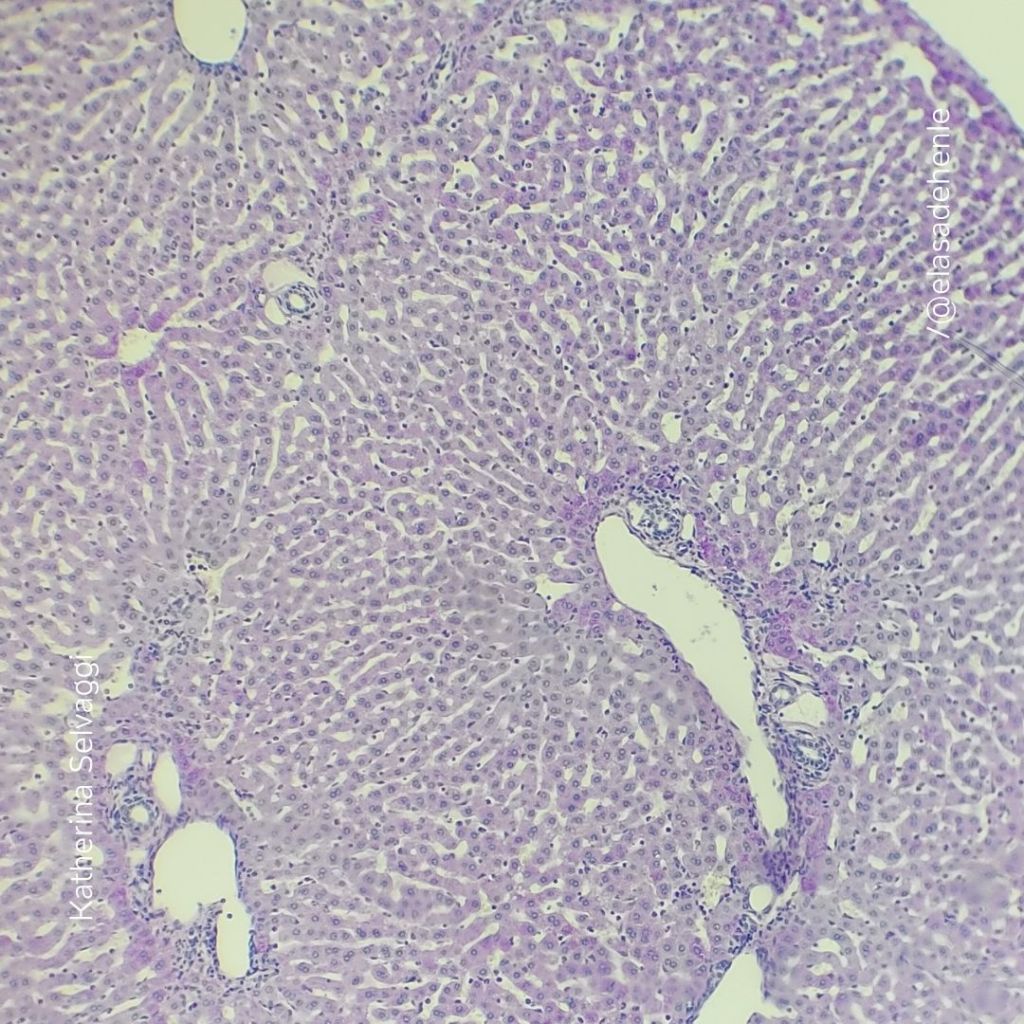

PAS – H

Hígado

Hospital de Clínicas